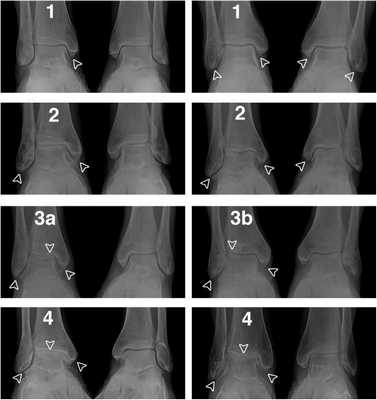

Рентгенологические стадии по Kellgren и Lawrence:

- 0 — полное отсутствие рентгенологических признаков;

- І — кистовидные изменения костной ткани, субхондральный линейный остеосклероз, краевые остеофиты небольшого размера;

- ІІ — сужение суставной щели, более выраженный остеосклероз;

- ІІІ — массивный субхондральный остеосклероз, сильное сужение суставной щели, остеофиты большого размера;

- ІV — массивные остеофиты, деформация эпифизов костей, практически полное отсутствие суставной щели.

Стадии остеоартроза голеностопного сустава

Классификация Н.С. Косинской:

- Начальная стадия. Характеризуется поражением только суставных хрящей. На рентгенограммах может визуализироваться незначительное сужение суставной щели, которое заметно лишь при сравнении с симметричным суставом.

- Стадия выраженных изменений. В дегенеративно-деструктивный процесс вовлекаются кости с развитием субхондрального остеосклероза. При рентгенографии выявляют краевые остеофиты и неравномерное сужение суставной щели как минимум на 50%.

- Стадия ярко выраженных изменений. Проявляется выраженным ограничением подвижности голеностопа. На рентгенограммах видны большие участки остеосклероза, массивные остеофиты, деформация костей и нарушение конгруэнтности суставных поверхностей.

В клинической практике в России и странах СНГ чаще всего используют классификацию Н.С. Косинской.